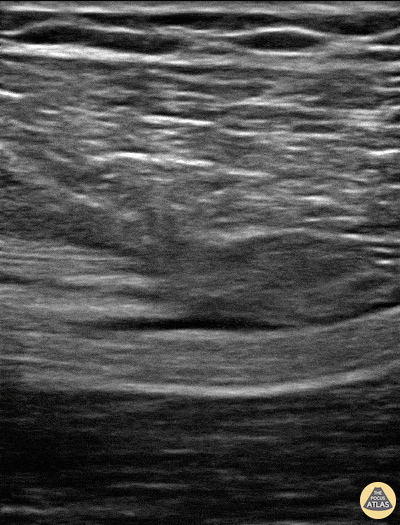

Patient sustained a gun shot wound through left mid thigh. Image is long axis view of sciatic nerve mid thigh. Nerve is running distal to proximal from left to right at approximately 3cm depth. There is a hypoechoic fluid collection seen superficial to the nerve. The epineurium is intact and we can see smaller nerve fibers contained in it. Patient had 0/5 plantar/dorsiflexion of ankle on admission, consistent with a sciatic nerve injury. The ultrasound exam on the sciatic nerve did not show any gross abnormality other than this fluid collection around the nerve. Within 7 days (4 days after this image) he regained strength in plantar/dorsiflexion in the ankle. Mike Guju, MD @MichaelMGujuMD Resident PM&R EVMS